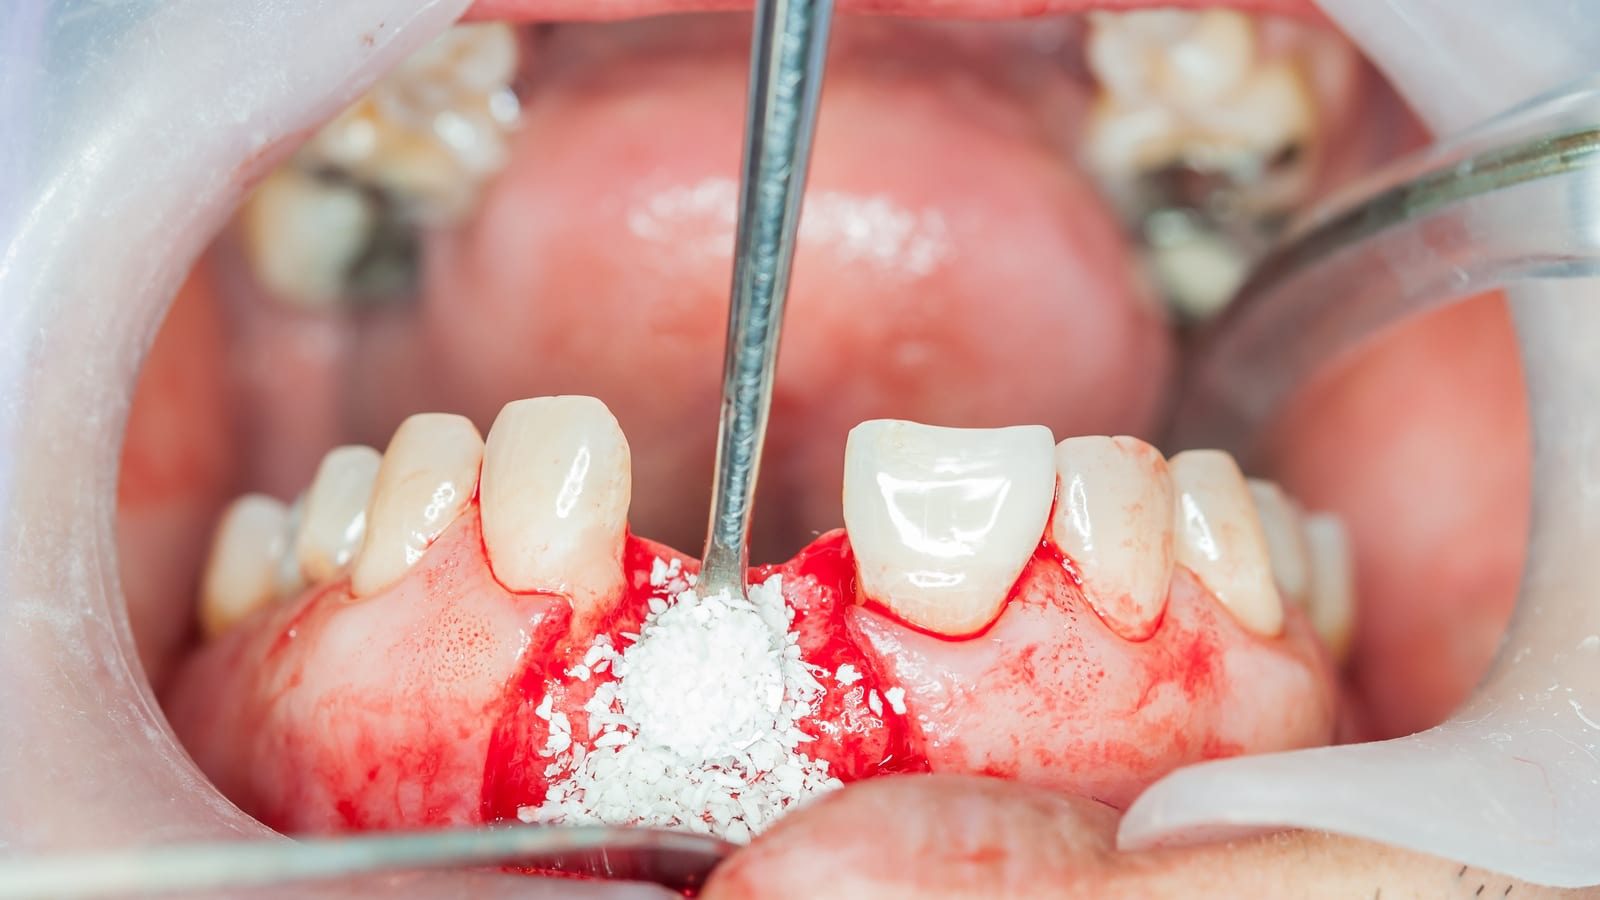

در بسیاری از بیماران به ویژه در نواحی خلفی ماگزیلا یا پس از گذشت مدت طولانی از کشیدن دندان، شرایط ایدهآل استخوانی وجود ندارد. در چنین مواردی استفاده از پودراستخوانی به عنوان یکی از رایجترین و موثرترین روشهای بازسازی، امکان اصلاح نقایص استخوانی و ایجاد بستری مناسب برای کاشت ایمپلنت را فراهم میکند. در واقع این مواد با نقش کلیدی خود در فرآیندهای القای استخوانسازی Osteoconduction و هدایت استخوان سازی Osteoinduction جایگاه مهمی در پروتکلهای بازسازی بافت سخت در دندانپزشکی یافتهاند.

پودر استخوان (Bone Graft Powder)مادهای است که برای بازسازی و افزایش حجم استخوان آلوئولار مورد استفاده قرار میگیرد. این مواد میتوانند از منابع مختلف مانند خود بیمار، انسان دیگر، حیوان یا به صورت سنتتیک تهیه شوند که در ادامه به آنها خواهیم پرداخت. هدف اصلی این پودر ایجاد بستری یرای تشکیل استخوان جدید و فراهم کردن حجم کافی برای کاشت ایمپلنت یا بازسازی نقصهای استخوانی است.

پودر استخوانی معمولا از بافت استخوان خرد شده به دست میآید و به صورت دانههای ریز در نواحی دچار کمبود استخوان قرار میگیرد و به عنوان یک ماده بیولوژیک با تحریک فرآیندهای ترمیمی به بازسازی استخوان کمک میکند. در واقع این ماده برای ترمیم ضایعات کوچک استخوانی مورد استفاده قرار میگیرد. در مقابل گرافت استخوانی به طور کلی به تودههای استخوانی با ساختار سهبعدی اطلاق میشود که میتواند از انواع مختلفی مانند بلوکهای استخوانی، گرافتهای ترکیبی با مواد مصنوعی ساخته شود. این گرافتها علاوه بر داشتن ویژگیهای پودر استخوانی، معمولا دارای ساختارهای بزرگتر و مقاومتری هستند که میتوانند در نواحی با کمبود شدید استخوان یا در فرآیندهای پیچیدهتر مانند لیفت سینوس و بازسازی استخوانهای فک استفاده شوند. در نهایت انتخاب میان پودر استخوانی و گرافت استخوانی بستگی به شرایط بالینی خاص، شدت کمبود استخوان و نیازهای ترمیمی هر بیمار دارد.

در مجموع میتوان گفت پودر استخوانی به عنوان یکی از پرکاربردترین مواد جایگزین در حوزه دندانپزشکی و جراحیهای فک و صورت، نقشی کلیدی در بازسازی و ترمیم بافتهای استخوانی ایفا میکند. این ماده نه تنها به عنوان یک داربست زیستی عمل کرده و محیط مناسبی را برای رشد و تکثیر سلولهای استخوان ساز فراهم میآورد بلکه در بسیاری از موارد طی فرآیند بازسازی تدریجی با استخوان طبیعی بدن جایگزین میشود. بدین ترتیب پس از گذشت چند ماه، ناحیه درمان شده دارای تراکم و استحکام کافی خواهد بود و شرایط ایدهآل برای قراردادن ایمپلنتهای دندانی ایجاد میگردد. استفاده از پودر استخوانی علاوه بر افزایش موفقیت درمانهای ایمپلنتولوژی، به بهبود زیبایی، عملکرد و پایداری طولانی مدت پروتزهای دندانی کمک شایانی میکند. بنابراین میتوان نتیجه گرفت که به کارگیری این ماده دردندانپزشکی مدرن، رویکردی علمی و کارآمد برای ارتقای کیفیت درمانهای بازسازی و جایگزینی دندان به شمار میرود.